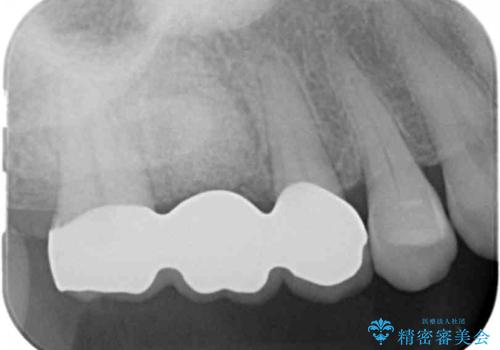

- 症状はないものの、検査の結果右上の奥歯が大きく割れていることが確認されたケースです。

無症状であったため放置していた結果、歯の周囲の骨が溶けてなくなっていました。

歯の深いところまで割れてしまっている場合は健康な状態での歯の保存ができないため抜歯の適応になります。